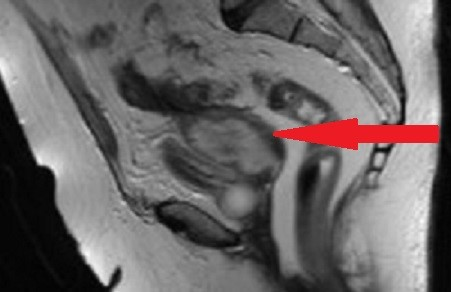

A 72-year-old woman was admitted to our emergency department with intermittent abdominal pain, diarrhea and fever up to 38.5°C for the last three days. The patient had a history of hypertension, dyslipidemia and alcoholism. She had one vaginal delivery in the past while her gynecological history was unremarkable. Her blood pressure was 100/70 mmHg, her pulse rate was 110 beats/min and her body temperature 38°C. The physical examination revealed mild sensitivity in palpation of the lower abdomen. Laboratory studies on her admission showed a white blood cell count of 25,000/µL (normal range 4–11x103/µl) with 79.3% neutrophilia (normal range 40–75%), crp 56 mg/dl (normal value <0.5) and creatinine 5.45 mg/dl (normal range 0.6–1.1 mg/dl) due to sepsis. Blood and urine culture was collected. Chest X-ray was normal. Ceftriaxone 2 gr twice daily and metronidazole 500 mg three times daily were administered promptly. The patient was observed in a high dependency unit for the first 3 days of hospitalization, but she was not intubated. The third day of her hospitalization, increased noisome vaginal discharge was observed and a gynecological assessment was requested. The optical examination of the cervix showed a purulent outflow through the cervical canal, and a pus culture was done. The pelvic exam revealed severe sensitivity in the lower pelvis. The transvaginal ultrasound examination showed an enlarged, integral uterus without any signs of perforation, hypoechoic fluid accumulation in the uterine cavity, unclear borders between endometrium – myometrium (Figure 1a [Fig. 1]), a mixed echogenic mass with a long axis of 38 mm in anatomical position of the right adnexa (Figure 1b [Fig. 1]) and no free fluid in the pouch of Douglas. The ultrasound findings were confirmed by a computed tomography (CT) with intravenous contrast, which demonstrated the presence of an air bubble in the uterine cavity, which was full of fluid, and a right tubo-ovarian abscess as well (Figure 2 [Fig. 2]). Cancer biomarkers for gynecological malignancy were negative. No bacteria grew from blood and urine cultures, whereas the vaginal pus culture grew Enterococcus faecia. The anti-bacterial medication was changed according to the antibiogram to tigecycline 50 mg iv twice daily. After three days of being fever free and improvement of the laboratory results (decrease of WBC to 11,000/mm3, crp to 4.83 mg/dl and creatinine to 0.71 mg/dl), the patient underwent ultrasound-guided dilatation and curettage of the cervical canal and the endometrium. The material that was collected was sent for histologic examination, which excluded malignancy. On the 10th day of hospitalization, the patient underwent magnetic resonance imaging (MRI) of the lower abdomen with intravenous contrast for the purpose of evaluation of pelvic inflammation, and demonstrated concrete improvement (Figure 3 [Fig. 3]). MRI was selected as a method of follow-up scanning because it offers excellent soft tissue contrast. Since our hospital does unfortunately not provide MRI scanning, MRI occurred at a private medical center. In addition, the patient was not re-examined sonographically because there was no specialist sonographer available. After fifteen days of hospitalization, the patient was discharged in an afebrile and hemodynamically stable condition, with the recommendation of per os antibacterial medication (clindamycin 300 mg three times daily for 14 days) and a second check in two weeks. The patient did not attend her scheduled appointment.

Gynecological assessment was only performed when vaginal discharge had been reported. The patient was treated conservatively since pyometra perforation or abscess rupture were excluded by imaging, and the dilatation of the cervix and drainage of the uterine contents combined with intravenous anti-bacterial administration definitely led to lysis of sepsis and the patient’s complete recovery. The dilatation of the cervical canal is the key to draining the purulent collection and preventing the abscess from rupturing into the peritoneal cavity. In combination with the intravenous administration of antibiotics, the inflammation was reduced and life-threatening complications were avoided. This fact is reflected in both the clinical picture and the laboratory exams. The repetitive imaging with MRI of the lower abdomen revealed articulate attenuation of pelvic disease. The patient was discharged on hospital day fifteen with follow-up.